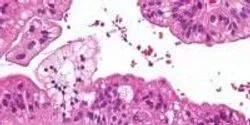

Researchers at the Virginia Bioinformatics Institute of Virginia Tech have discovered new possibilities for detecting ovarian cancer using microsatellite variations.